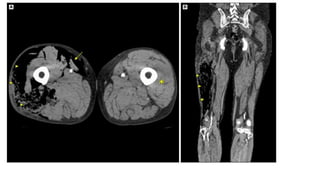

This document discusses necrotizing soft tissue infections such as necrotizing fasciitis. It notes that these infections can originate from trauma, surgery, immunosuppression or malignancy. They can be polymicrobial, involving multiple organisms, or monomicrobial, involving an aggressive single organism. Diagnosis involves history, examination, and imaging tests. Differential diagnoses include deep vein thrombosis, pyomyositis, pyoderma gangrenosum, and cellulitis. Treatment involves stabilization, broad spectrum antibiotics, debridement of infected tissue, and reconstruction.